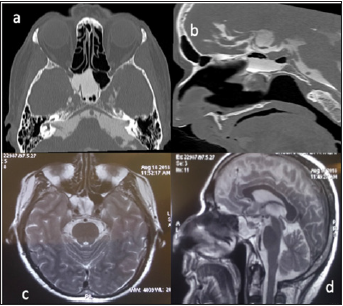

A 57-year-old man referred for clear watery discharge from the right nostril of no obvious cause. He suffered from intermittent rhinorrhea starting 6 months prior to arrival. He reported recent history of bacterial meningitis one month ago, which was treated successfully at an outside hospital. On admission, he had no focal neurological deficits. Nasal fluid tested positive for beta2 transferrin. Brain MRI revealed that the right sphenoid sinus was filled with CSF (Figure 4). CT cisternography showed that the contrast material passed from the prepontine cistern into the sphenoid sinus through this bone defect in the clivus. (Figure 4). After intrathecal administration of 0.25 mL of 10% fluorescein with 10 mL of cerebrospinal fluid the patient underwent endoscopic trans nasal approach. After stripping the mucosa from posterior wall of sphenoid sinus, CSF leak was observed in the upper region of clivus just below the sella at the midline (Figure 5). The defect was closed by abdominal fat and reinforced by fascia lata and naso septal flap. At the During 30-month follow-up appointment, no signs of recurrence were found. In both of the above reviewed cases, a lumbar drain was not placed pre or postoperatively.

Figure 4: (a) CT Cisternography showing right sphenoid sinus filled with CSF and (b) the entry of cerebrospinal fluid into the sphenoid sinus. (c) axial T2 weight MRI revealed right sphenoid sinus filled with CSF (d) CSF leakage from prepontine cistern to sphenoid sinus.